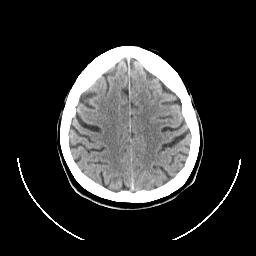

CT Study #1 -- Slice #22